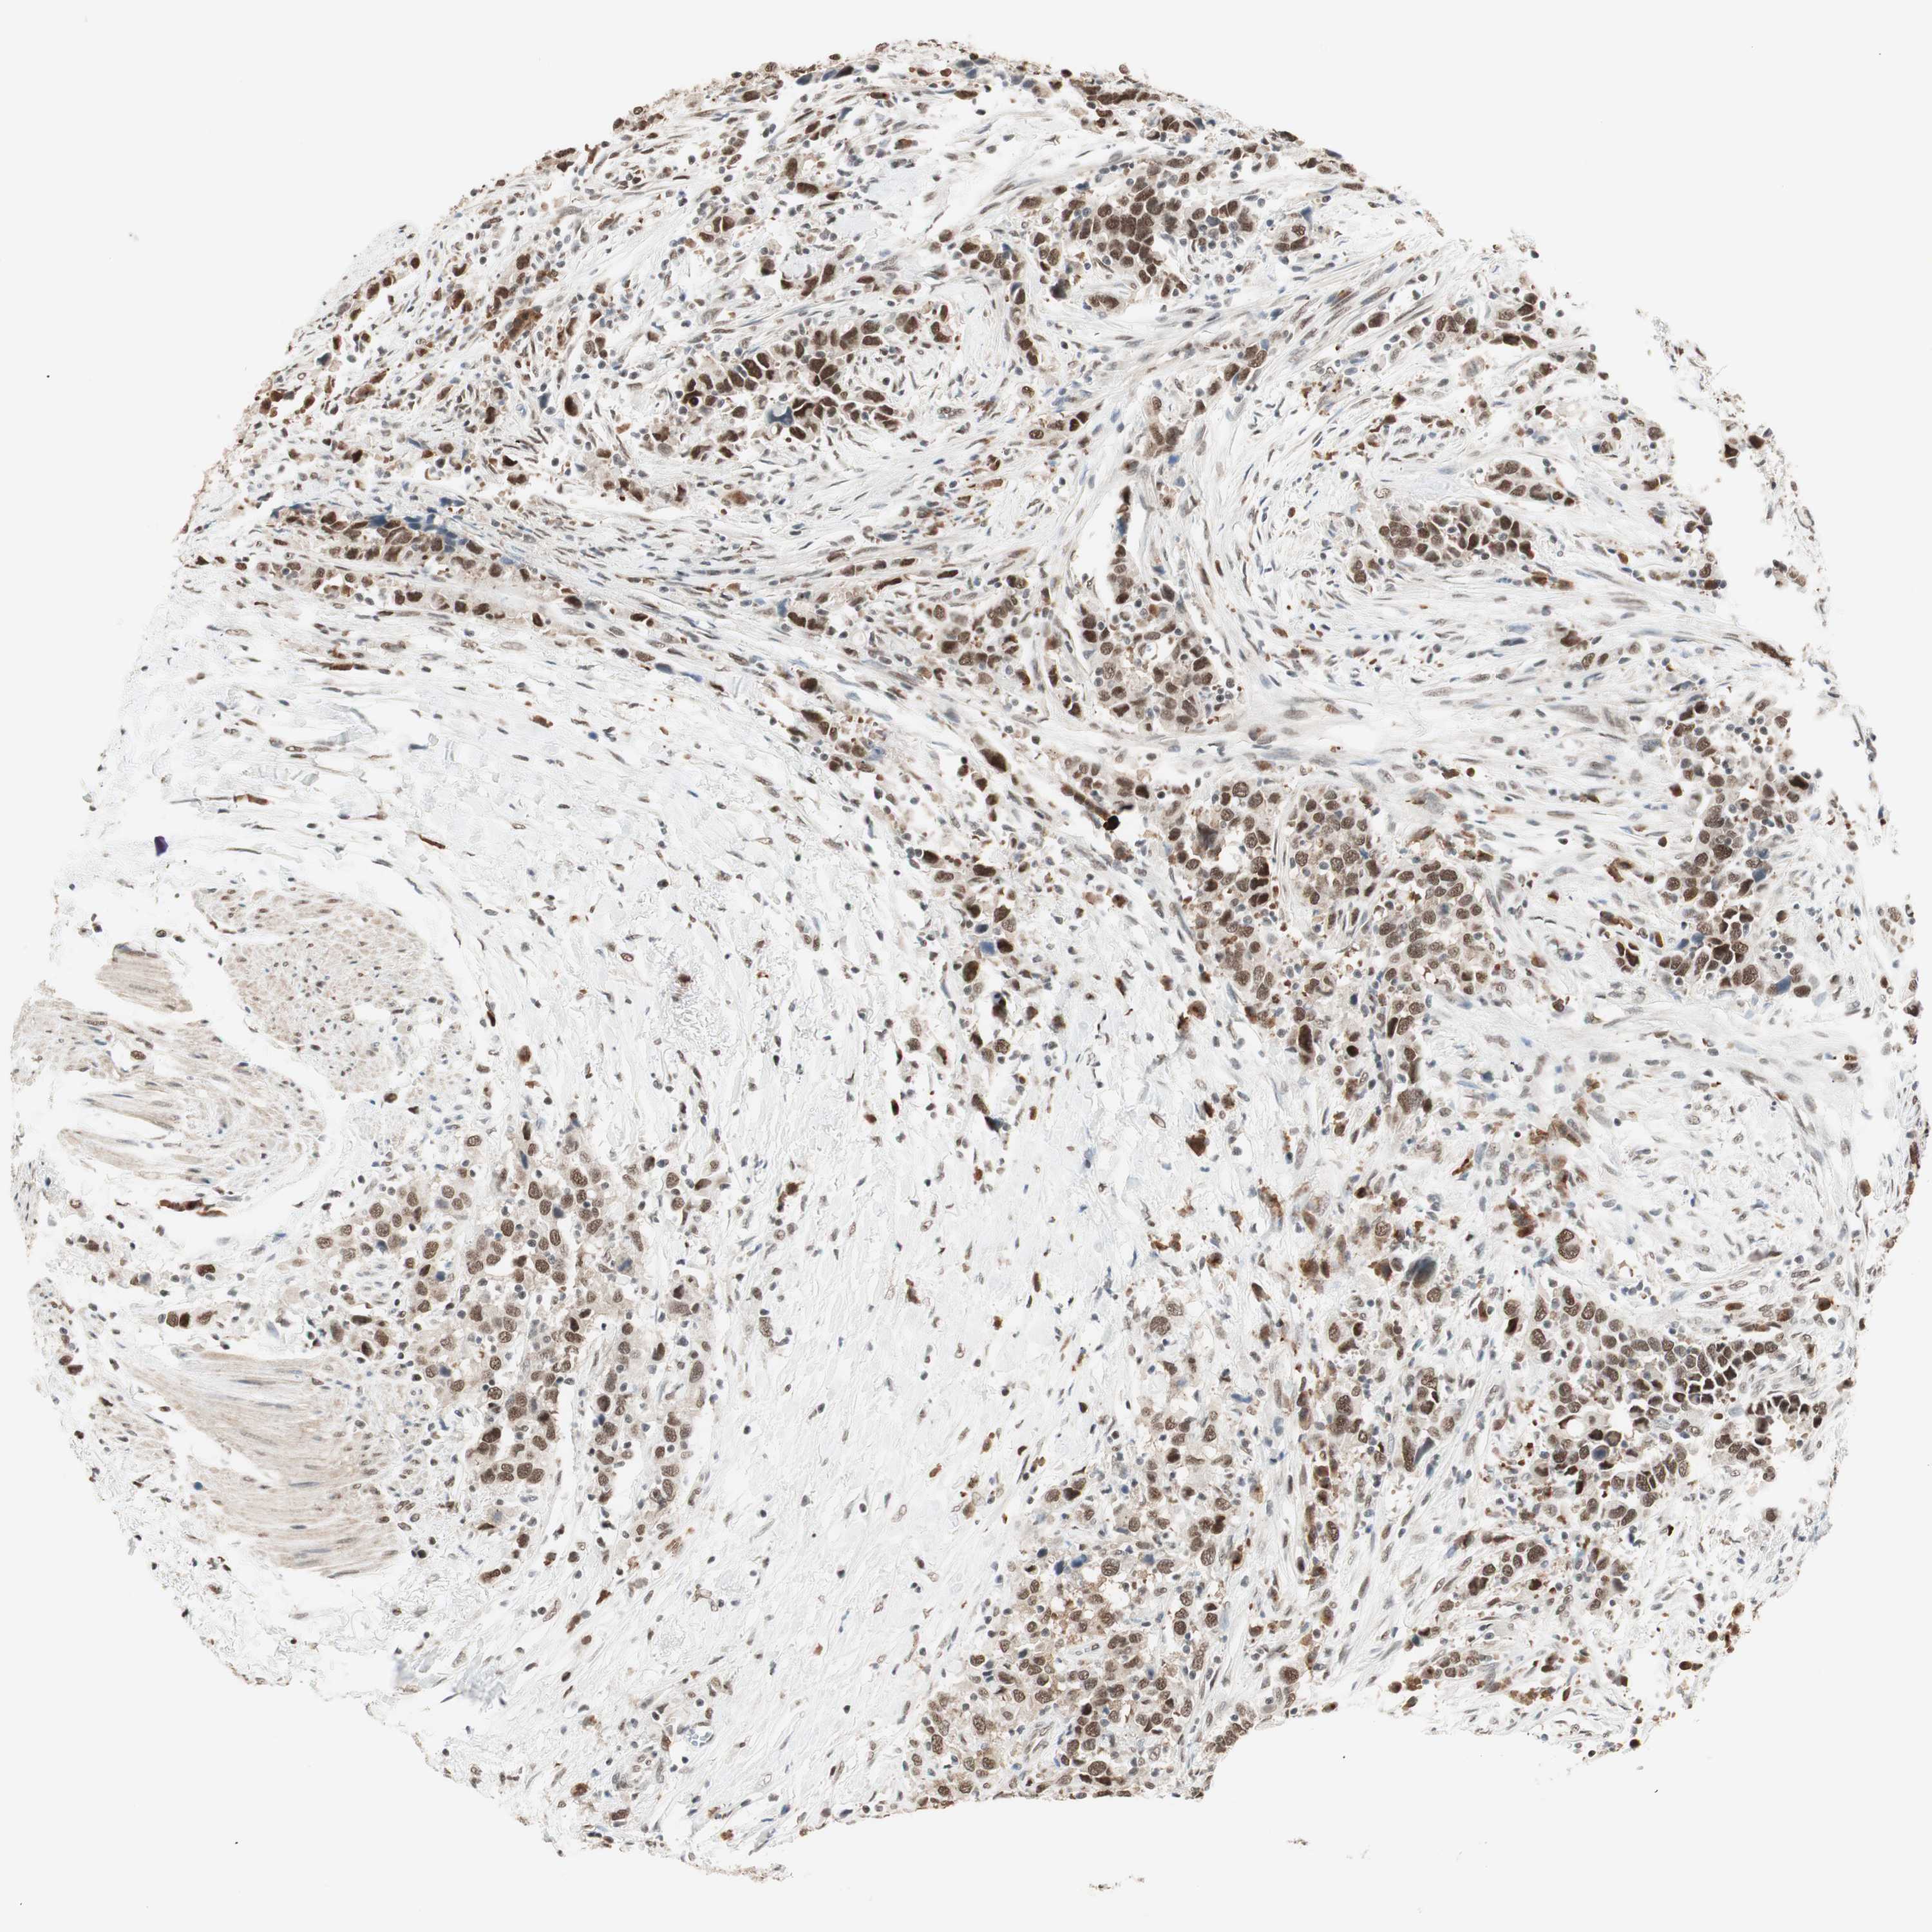

UROTHELIAL CANCER - Protein expressioni

A mouse-over function shows sample information and annotation data. Click on an image to view it in a full screen mode. Samples can be filtered based on level of antibody staining by selecting one or several of the following categories: high, medium, low and not detected. The assay and annotation is described here.

Antibody stainingi

Antibody staining in the annotated cell types in the current human tissue is reported as not detected, low, medium, or high, based on conventional immunohistochemistry profiling in selected tissues. This score is based on the combination of the staining intensity and fraction of stained cells.

Each image is clickable and will lead to virtual microscopy that enables deeper exploration of all samples and also displays staining intensity scores, fraction scores and subcellular localization as well as patient and tissue information for each sample.

Antibody HPA003916

Antibody CAB037318

Staining

High

Medium

Low

Not detected

Intensity

Strong

Moderate

Weak

Negative

Quantity

>75%

75%-25%

<25%

None

Location

Nuclear

Cytoplasmic/membranous

Cytoplasmic/membranous,nuclear

Urothelial carcinoma, Low grade

Urothelial carcinoma, High grade

Urothelial carcinoma, NOS